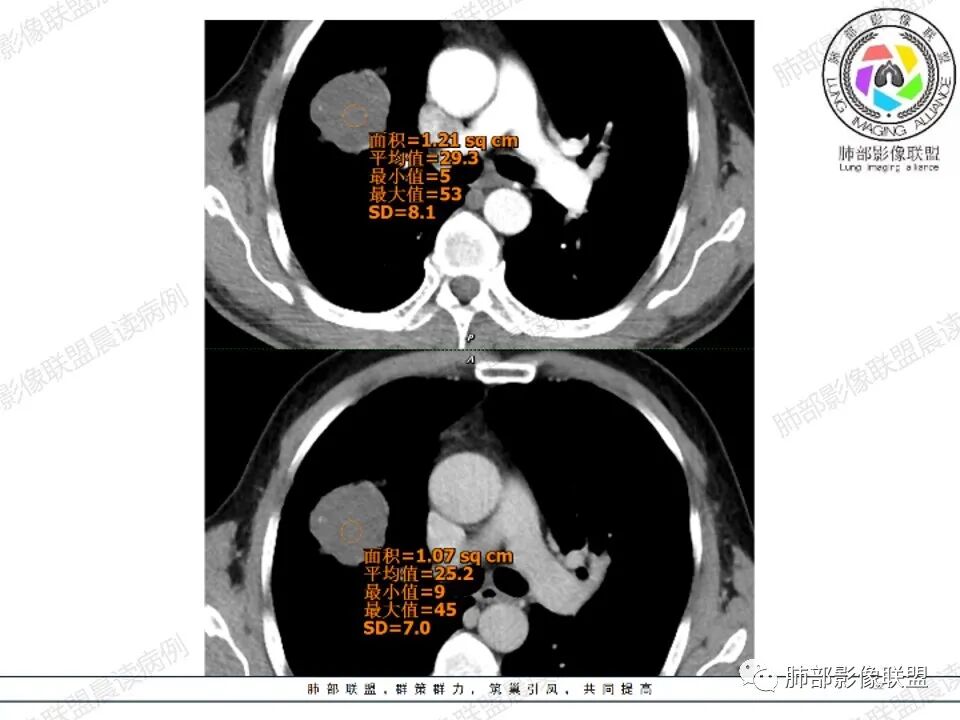

右肺上叶见一分叶状结节,增强扫描未见明显强化,考虑1.错构瘤2.支气管囊肿。

右上肺孤立性肿块性影,形态规则,边界清,密度25HU左右,没有点状钙化样密度,未见明确强化,周围可见条索,内缘肺透过度增强,有一副裂发育,考虑发育异常,支气管囊肿,CT值略高考虑合并感染;支气管闭锁,邻近未见明确支气管通行可排除;错构瘤,无强化应该是软骨型错构瘤,但是钙化太少,也可以排除;肿瘤,无强化可基本排除;结核球,不出除外

中年男性,右上肺类圆形肿块影,边缘膨隆,无明显分叶毛刺,内可见点状钙化,肿块整体密度较低,增强CT值才25HU左右(说明强化不明显或根本没有强化),周围可见少许斑片索条影,考虑良性病变,首选支气管囊肿,鉴别错构瘤。

3.影像表现:支气管粘液栓(形态沿支气管树分布的铸型结构,可呈分支状、圆形、椭圆或分叶状,多为水样密度,蛋白含量较高时可类似软组织密度,增强无强化),周围不同程度的肺气肿,可伴发感染。

3.影像表现:表现为肺实质内圆形或类圆形、边缘光整的病灶,囊内密度一般为水样密度,部分因合并蛋白、钙质、粘液,或者出血时可呈较高密度,若含液囊肿与支气管相通、囊液排除,则形成气液囊肿或含气囊肿;囊壁均匀,部分囊壁可见弧形钙化,合并感染时囊壁可见明显增厚、强化,并可出现液气平,但治疗后病变可见有明显变化。

相对低密度,边界清楚规整,有囊壁感,或伴钙化,内容物不强化等具有强烈提示意义。